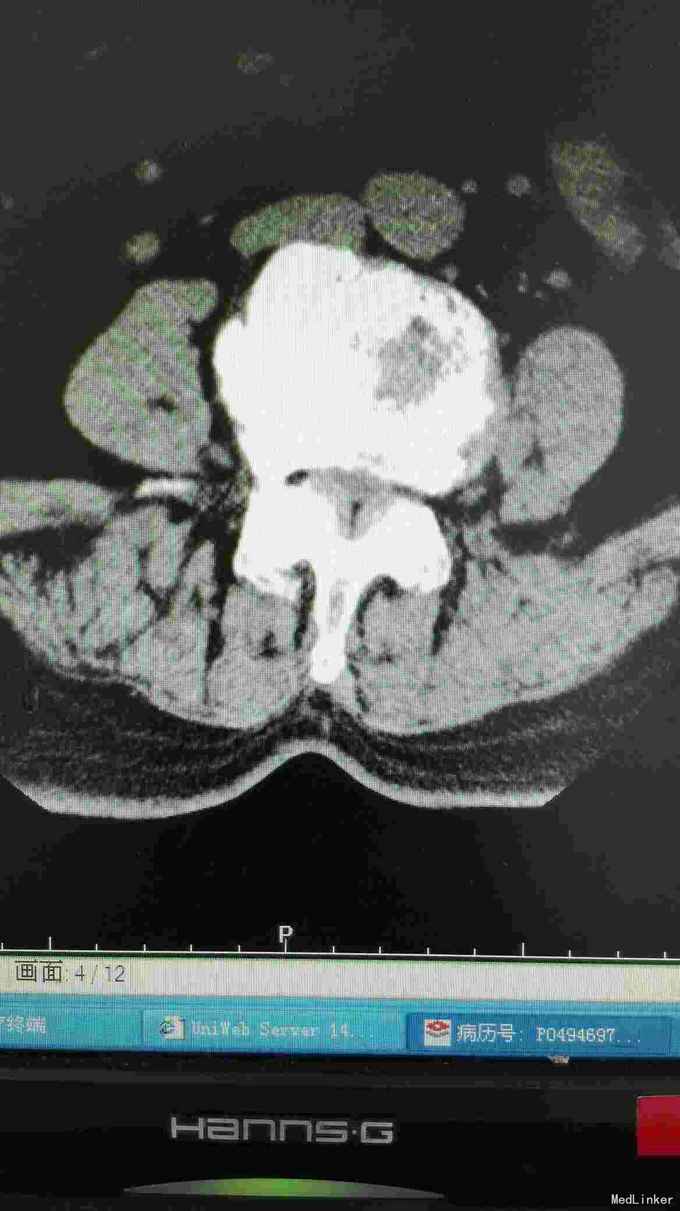

患者腰部疼痛伴右下肢疼痛麻木2年,间隙性跛行。

腰椎影像检查提示椎间盘突出,椎管狭窄,退变侧弯。

诊断腰椎间盘突出症,腰椎管狭窄症,腰椎退变性侧弯。 在全麻下行腰椎固定,减压,畸形矫正融合术。